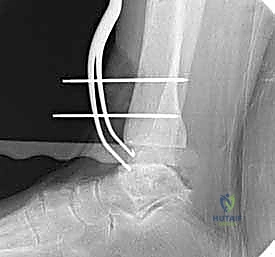

- الأشعة السينية الحاملة للوزن (Weight-Bearing X-rays): هي المعيار الذهبي المبدئي. تظهر تضيق المسافة المفصلية، تكون النتوءات العظمية (Osteophytes)، والتكيسات العظمية (Subchondral cysts).

- الأشعة المقطعية (CT Scan): ضرورية جداً للتخطيط الجراحي، حيث تعطي صورة ثلاثية الأبعاد لحجم العظام وجودتها، وتساعد في تحديد حجم غرسة STAR بدقة.

- المكون الظنبوبي (Tibial Component): صفيحة معدنية مسطحة من سبائك الكوبالت والكروم (Cobalt-Chromium)، تُثبت في أسفل عظمة الساق (الظنبوب) بواسطة أسطوانتين معدنيتين تدخلان في العظم لضمان الثبات المطلق.

- المكون الكاحلي (Talar Component): قطعة معدنية تغطي قبة عظم الكاحل، مصممة بشكل تشريحي منحني يحاكي تماماً شكل العظمة الأصلية، وتحتوي على أخدود طولي.

- الحشوة البلاستيكية المتحركة (Mobile Polyethylene Bearing): هذا هو سر نجاح غرسة STAR. هي قطعة من البلاستيك الطبي عالي الكثافة (UHMWPE) توضع بين القطعتين المعدنيتين. هذه القطعة ليست ثابتة، بل تنزلق بحرية للأمام والخلف، وتسمح بدرجة طفيفة من الدوران. هذا التصميم "المتحرك" يقلل بشكل هائل من إجهاد القص (Shear Stress) على واجهة العظم والمعدن، مما يقلل من احتمالية تخلخل الغرسة (Loosening) على المدى الطويل، ويمنح المريض نطاق حركة فسيولوجي مذهل.

تعتمد دقة الجراحة على المحاذاة الصحيحة. يتم استخدام أجهزة توجيه متطورة (Jigs) تثبت على عظمة الساق باستخدام دبابيس معدنية. يتم التحقق من صحة الزوايا والمحاور باستخدام جهاز الأشعة السينية المباشر داخل غرفة العمليات (C-arm Fluoroscopy). يضمن الدكتور هطيف أن يكون القطع موازياً للأرض تماماً عند وقوف المريض.